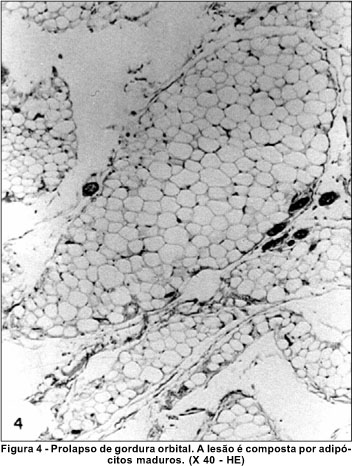

Apesar da aparência clínica semelhante, as duas entidades diferiram ao exame histopatológico. O dermolipoma foi visto como uma lesão coberta por epitélio escamoso estratificado, com estroma subepitelial contendo feixes de tecido colágeno denso, onde foi observado em um dos pacientes a presença de estruturas pilosebáceas (Figura 3A). No estroma profundo, presença de tecido adiposo disposto em lóbulos separados entre si por traves de tecido colágeno denso (Figura 3B). Já, o prolapso de gordura orbital foi visto como composto por adipócitos maduros (Figura 4).

A superfície epitelial é freqüentemente fina e lisa, mas ocasionalmente surgem irregularidades; epitélio é escamoso estratificado e parcialmente queratinizado; o estroma contém feixes de colágeno denso, similar ao do dermóide límbico. Estruturas pilosebáceas podem ser raramente observadas. Em algumas lesões o estroma contém cartilagem e glândulas ácinas(9). Já, o prolapso de gordura orbital corresponde histologicamente a apenas adipócitos maduros, dispostos em lóbulos.